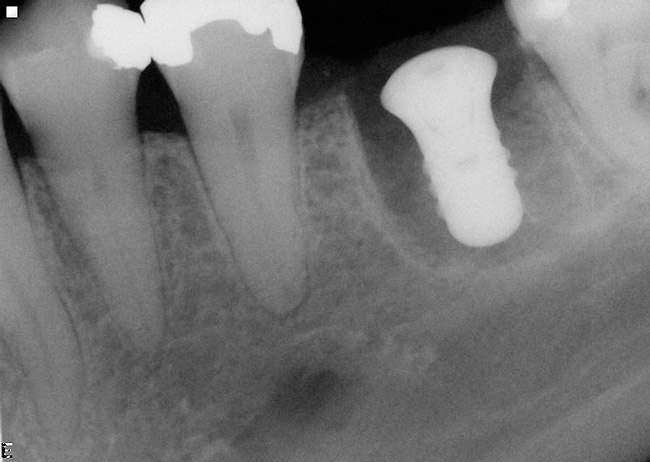

Implant placement at the time of mandibular molar extraction should never be attempted if there is any doubt about the ability to place an ideal dimension implant in the appropriate restorative position and attain primary stability. In such a situation it is better to first perform regenerative therapy at the time of tooth removal and place the implant in a subsequent surgical session (Figure 2 through Figure 4).

All mandibular multi-rooted teeth are hemisected (or trisected in the rare cases of three-rooted mandibular molars) prior to removal. In such cases, a piezosurgical approach is utilized, in conjunction with specifically designed periotomes, to effect atraumatic tooth extraction. If such therapy is performed appropriately, the net result is an extraction socket whose alveolar morphology has been no further compromised through the act of tooth removal. In situations where high-speed rotary instrumentation must be used to help retrieve fractured root portions, the site is deemed no longer amenable to immediate implant placement due to the excessive trauma having been placed on the alveolar bone in the area. Regenerative therapy is performed employing appropriate graft materials and covering membranes, and the implant is placed in a second surgical visit. Such instances are rare.